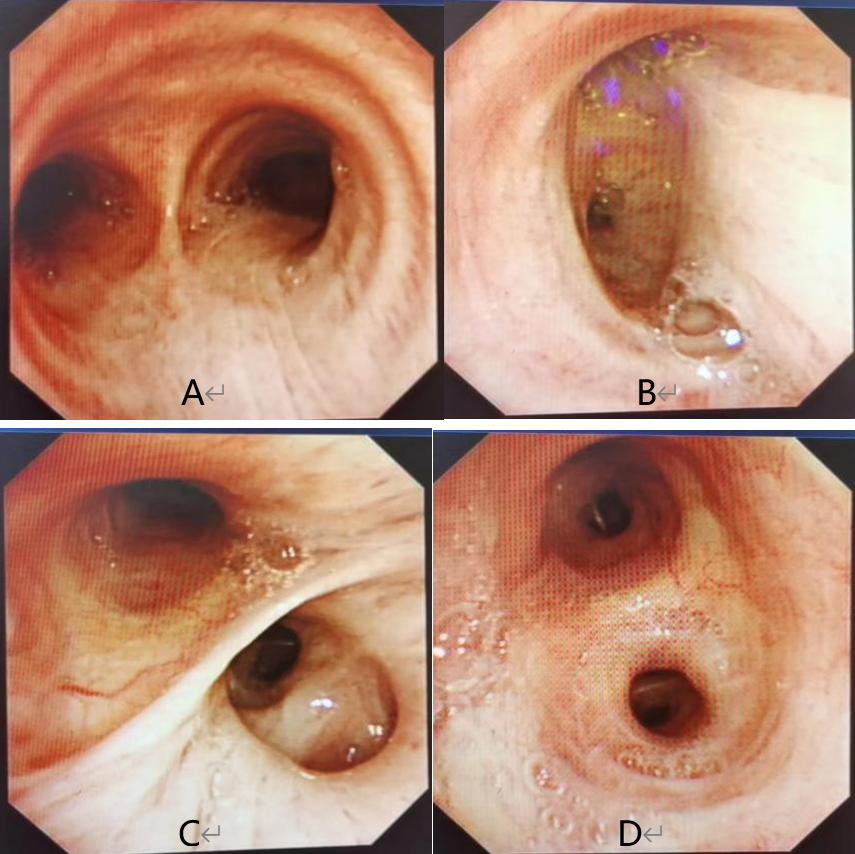

图3:2022年8月11日患者的气管镜检查

A 隆突B 右主支气管C 右中叶、下叶支气管D 左上叶支气管

治疗后患者胸闷、气喘症状较前稍缓解。为了进一步明确病原学,2022年8月11日行支气管镜检查(图3),镜下未见明显异常,于左固有上叶以20ml生理盐水行肺泡灌洗,回收灌洗液15ml分别行细菌学、真菌学、抗酸检验和mNGS检测。请看第四份卷宗,入院后的部分化验结果: